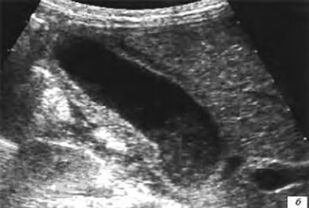

Учебное пособие посвящено одной из актуальнейших проблем детской гастроэнтерологии - методам исследования желудочно-кишечного тракта. В первой части пособия представлены анатомо-физиологические особенности развития органов желудочно-кишечного тракта, подробно описаны методики осмотра пациентов, особенности сбора жалоб и анамнеза гастроэнтерологических заболеваний у детей разных возрастных групп. Оснащено тестовыми заданиями и ситуационными задачами с эталонами ответов, приложениями.